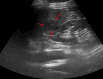

Figure 1. Gray-scale axial abdominal ultrasonography examination

At the level of the splenic hilum, a nodular lesion measuring approximately 26x29 mm with mildly lobulated contours is observed. It appears iso-hypoechoic compared to the surrounding splenic parenchyma (red arrows).